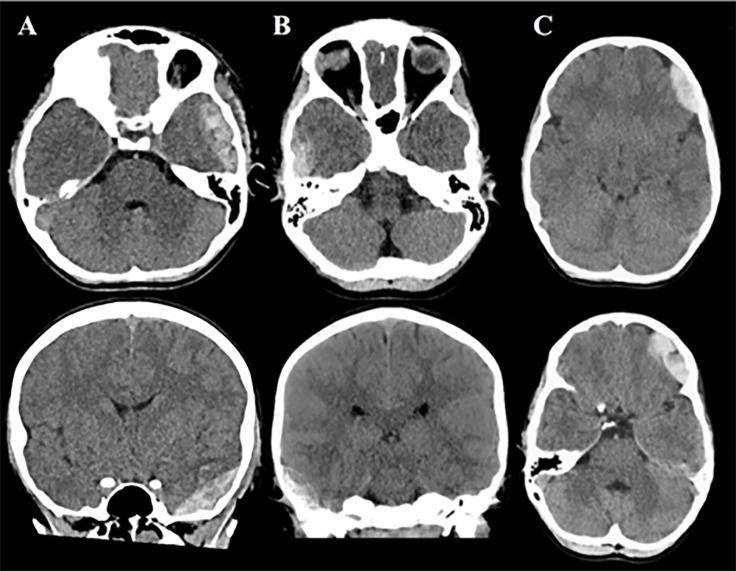

Eligible patients were those <18 years old who were admitted to the emergency department at three academic children's hospitals with head trauma and who received a clinically indicated head computed tomography (HCT). Measurements were obtained by a blinded operator in bilateral frontal, temporal, parietal, and occipital regions. Qualifying hematomas were a priori determined to be within the brain scanner's detection limits of >3.5 milliliters in volume and <2.5 centimeters from the surface of the brain. The device's measurements were positive if the difference in optical density between hemispheres was >0.2 on three successive scans. We calculated diagnostic performance measures with corresponding exact two-sided 95% Clopper-Pearson confidence intervals (CI). Hypothesis test evaluated whether predictive performance exceeded chance agreement (predictive Youden's index > 0).

A total of 464 patients were enrolled and 344 met inclusion for primary data analysis: 10.5% (36/344) had evidence of a hematoma on HCT, and 4.7% (16/344) had qualifying hematomas. The handheld brain scanner demonstrated a sensitivity of 58.3% (21/36) and specificity of 67.9% (209/308) for hematomas of any size. For qualifying hematomas the scanner was designed to detect, sensitivity was 81% (13/16) and specificity was 67.4% (221/328). Predictive performance exceeded chance agreement with a predictive Youden's index of 0.11 (95% CI, 0.10 - 0.15; P < 0.001) for all hematomas, and 0.09 (95% CI, 0.08 - 0.12; P < 0.001) for qualifying hematomas.